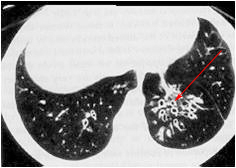

What is the pathology which is seen in this image?

Bronchiectasis

What is the classification of this pathology?

inflammatory and degenerative

The pathology in this image is seen radiographically as

Diluted and fluid filled bronchioles